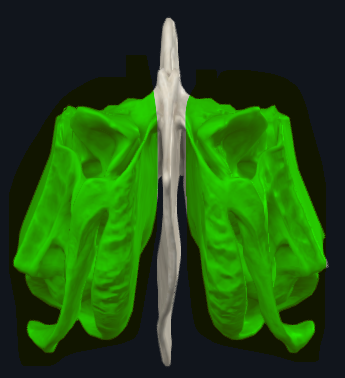

Celdillas etmoidales

Cavidades neumáticas. Dan volúmen con poca masa al cráneo.

Parte de los senos paranasales.

Contiene muchas cavidades neumáticas

Celdillas etmoidales, se dividen en anteriores y posteriores

Meato superior

Las celdas etmoidales POSTERIORES drenan a este meato

Meato medio

Las celdas etmoidales ANTERIORES, el seno frontal y el seno maxilar drenan a este meato